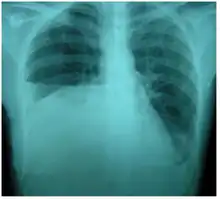

Right sided pleural effusion caused by urinothorax

Chest X-ray showing urinothorax disappearing after treatment

Treatment mainly consists of treating the underlying disorder of the genitourinary tract.[2] It requires a multidisciplinary team that includes a pulmonologist and urologist. A nephrostomy tube or Foley catheter can be used to relieve any underlying obstruction. Any injuries are repaired.[11] When the underlying disorder is addressed, the urinothorax rapidly resolves. Thoracic surgery is usually not needed,[4] especially if respiratory symptoms are minimal or nonexistent.[2] Pleurodesis is also ineffective.[11] A chest tube can be used to drain urine from the pleural cavity.[12]